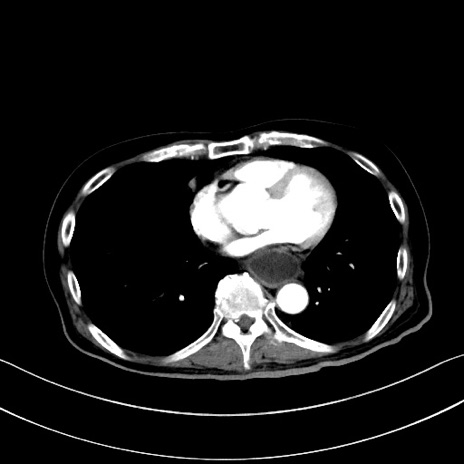

冠状断像

【症例】60歳代男性

【主訴】嘔吐

【現病歴】胃癌にて胃全摘後。食思不振が悪化し、夜中に嘔吐することがある。

【既往歴】胃癌、胃全摘、脾摘、胆摘後

【データ】WBC 5900、CRP 10.56